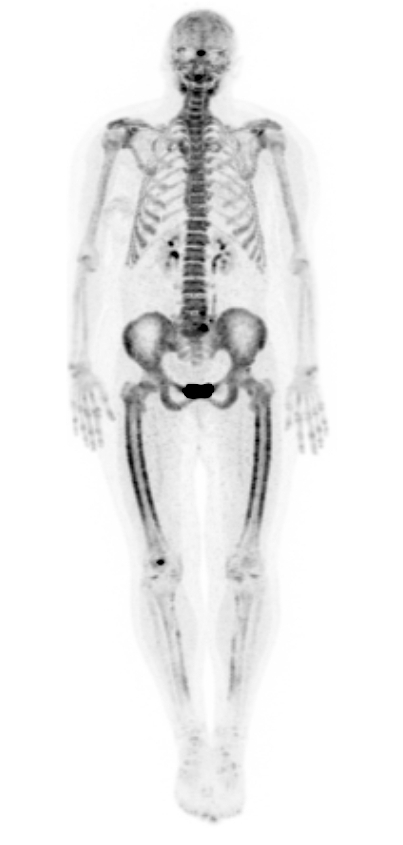

Hypertrofische osteoartropathie (ziekte van Pierre Marie-Bamberger, ziekte van Marie-Bamberger, secundaire hypertrofische osteoartropathie) wordt gekenmerkt door overmatige vorming van huid en bot aan de distale uiteinden van vingers en tenen, leidend tot clubbing (trommelstokvingers). Ook aan andere beenderen kan een periostreactie worden gezien op röntgenfoto’s en botscintigrafie. De DD van onderliggende oorzaken is groot, maar bij 80-90% speelt een onderliggend longcarcinoom.

Marie-Bamberger PET-CT-scan

PET-Scan: Drahreg01 - Wikimedia (Creative Commons License 3.0).